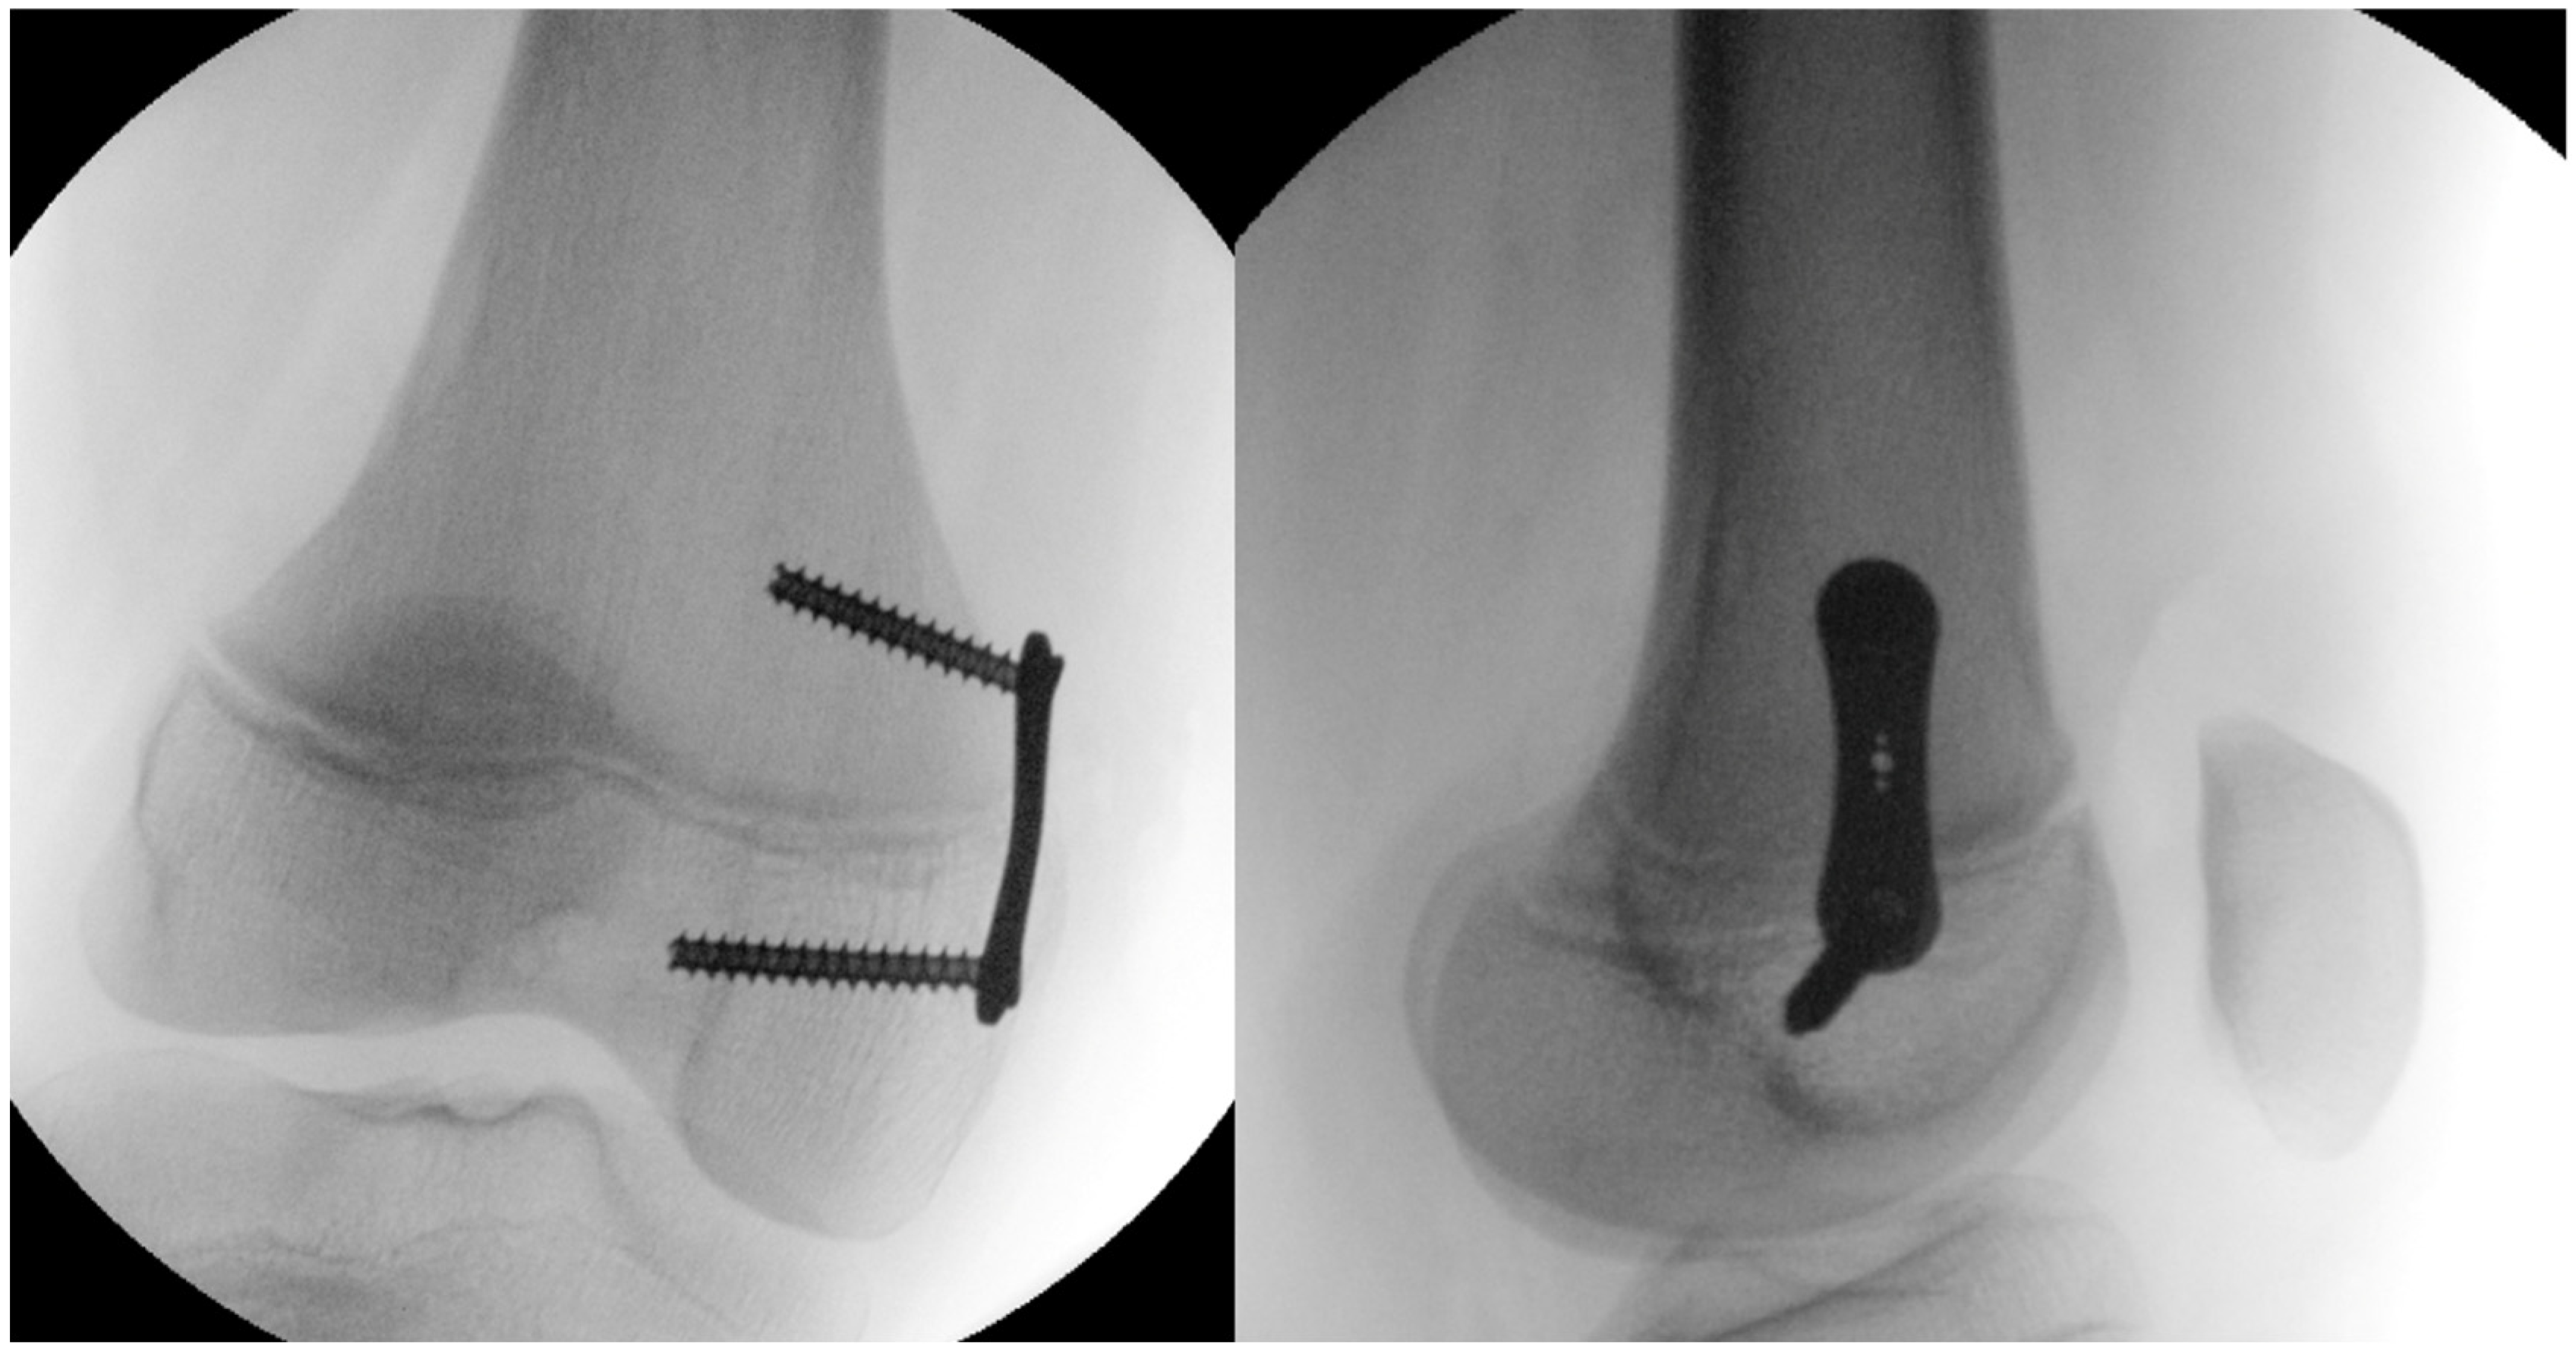

2.4. Surgical Technique

All procedures were performed with the patient in the supine position under fluoroscopic guidance. First, the physis was localized and marked with a Kirschner wire, with radiographic confirmation in two planes. The periosteum was then exposed to prepare the plate bed, after which the tension band plates was advanced over the positioned Kirschner wire and secured using cancellous screws (Figure 4).

Figure 4. Postoperative biplanar radiographic evaluation of a temporary medial distal femoral hemiepiphysiodesis.